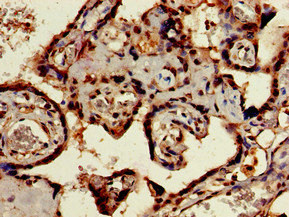

Immunohistochemistry of paraffin-embedded human placenta tissue using CSB-PA896485LA01HU at dilution of 1:100